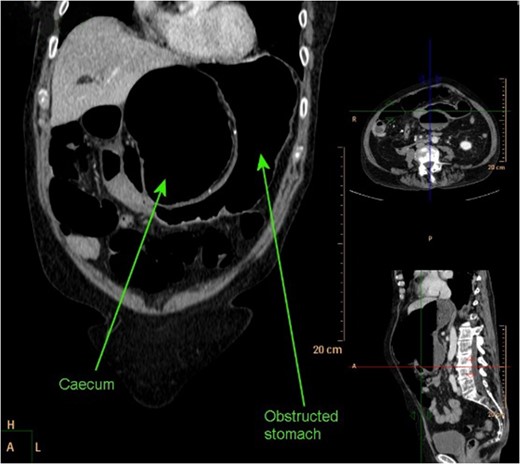

CT abdomen coronal reconstruction demonstrating obstructed stomach with obstructed and dilated caecum present in lesser sac.